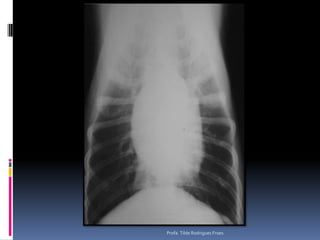

Exame radiográfico torácicoCuidados – padrões eventualmente detectados – diferenciação da sua relevânciaSilhueta cardíacaAumentos verdadeiros (posicionamento) x Gordura mediastinal – velhinhos obesosComo diferenciar (3 projeções)Gatos velhos – RX – “coração preguiçoso”Dificuldades na avaliação – escolha a Projeção VDProfa. Tilde Rodrigues Froes

Exame radiográfico torácicoCuidados – padrões eventualmente detectados – diferenciação da sua relevânciaASPECTOS RELEVANTESAumento do Átrio esquerdo (Endocardiose de mitral)Aumento generalizado (Miocardiopatia x efusão pericárdica x massa)Imagem de “D”Invertido – associado a quadros pulmonares e colapso de traquéiaProfa. Tilde Rodrigues Froes

Exame radiográfico torácicoCuidados– padrões eventualmente detectados – diferenciação da sua relevânciaSilhueta cardíacaAumentos verdadeiros (posicionamento) x Gordura mediastinal – velhinhos obesosComo diferenciar (3 projeções)Gatos velhos – RX – “coração preguiçoso”Dificuldades na avaliação – escolha a Projeção VDProfa. Tilde Rodrigues Froes

Exame radiográfico torácicoCuidados– padrões eventualmente detectados – diferenciação da sua relevânciaASPECTOS RELEVANTESAumento do Átrio esquerdo (Endocardiose de mitral)Aumento generalizado (Miocardiopatia x efusão pericárdica x massa)Imagem de “D”Invertido – associado a quadros pulmonares e colapso de traquéiaProfa. Tilde Rodrigues Froes